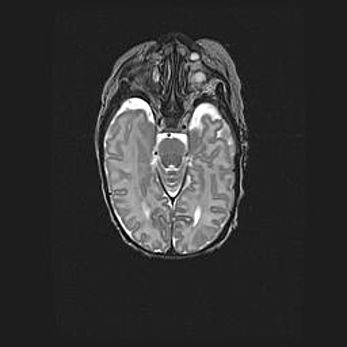

Наружная гидроцефалия с возможной атрофией височных областей.

Возраст: 28 дней

Вес: 3670 г

Пол: мужской

Окружность головы: 38 см

Срок гестации: 40 недель

Гидроцефалия головного мозга у новорожденных – это заболевание, которое характеризуется скоплением избыточного количества спинномозговой жидкости в желудочковой системе головного мозга в результате затруднения её перемещения от места выработки к месту поглощения в кровеносную систему или вследствие нарушения абсорбции. При открытой наружной форме гидроцефалии у новорожденных расширяются и переполняются субарахноидные пространства.

При нормотензивных  формах,  которые,  как  правило,  являются  следствием  перенесенных ишемических  повреждений  паренхимы  мозга,  возможно  сочетание микроцефалии  с нормотензивной гидроцефалией. В основе данных изменений лежит атрофия больших полушарий с преимущественной  локализацией  в  лобно-височных  областях.